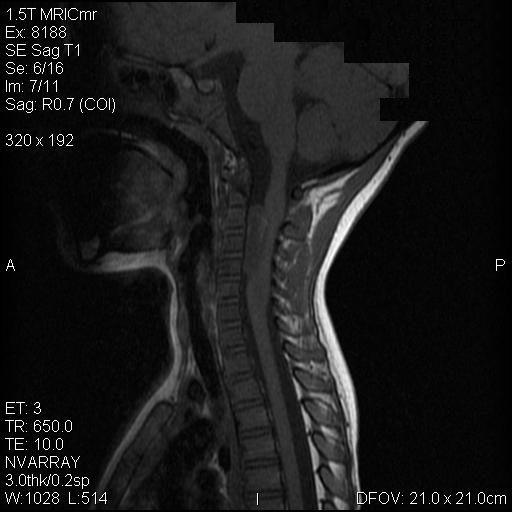

Clinical information: The patient was a 4 year-old girl who was in good health. She had difficulties with her left upper extremity for about a week. The problem progressed to her right upper extremity and later to her lower extremities. In a few days, she became quadriplegic. Her sensory functions remained intact. MRI imaging revealed a large intradural, extramedullary contrast enhancing mass that extended from cervical spine C2 to C6 in the anterior aspect of her spinal canal. The tumor also extended through and expanded the foramen on the left nerve roots. Systemic investigation did not reveal any neoplastic disease in other system. The tumor was excised. The followings are representative images of this case.

On T1-weighed images, the lesion appeared as a sausage-shaped mass that runs along the long axis of anterior portion of a spinal canal with marked compression of the spinal cord. The mass is well defined from the spinal cord and suggest an intradural, extramedullary location (Panel A). The mass abuts and slightly displaces the left vertebral artery forward. While the intracanalicular portion of the mass is well marginated, the anterolateral, extracanalicular component shows mild infiltration of the musculature. There is slightly heterogeneous enhancement of the mass. Some dural tail enhancement is also present (Panel B). On axial plane, extension of the mass through neuroforamens is well demonstrated (Panel C).